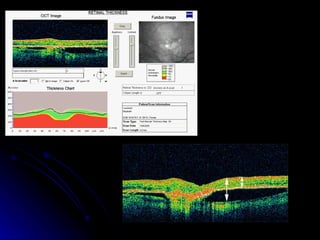

Retinal Thickness Analysis   Using the retinal thickness analysis tool, the software then traces a line along the NFL layer and a line along the RPE layer.  The software then measures the distance between the two lines and a graph is produced which compares the measured thickness to the thickness of a normal retina

Each of the six scans can be reviewed by clicking on the slider bar to the left, and any or all of them can be printed out for the patient's record

Retinal thickness analysis does not measure retinal  elevation   for example this eye with a pigment epithelial detachment (PED) pictured below.  The arrow on the left would represent retinal elevation, from the choroid, through the fluid space of the PED, to the nerve fiber level.  The arrow on the right shows what the analysis measures, defined by the distance from the RPE (which is detached) to the NFL